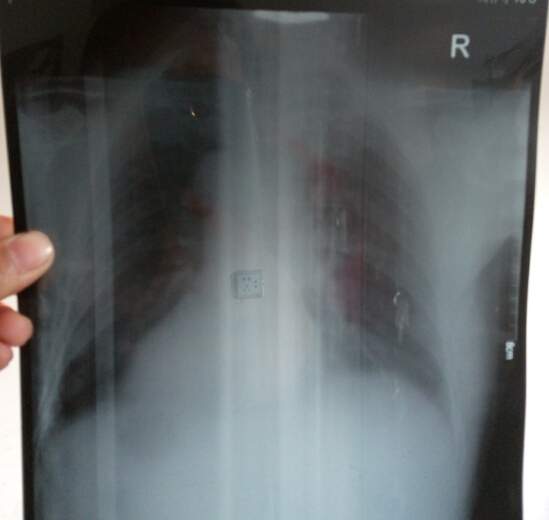

求详细分析两张体检单,金币不是问题哦 已有4人参与

感谢参与,应助指数 +1 2的897: 金币+50, ★★★很有帮助, 发50个,很真诚的评论,希望能帮忙多叫几个同专业的看看,因为医院的医生感觉忽悠的多 2016-02-24 12:42:58